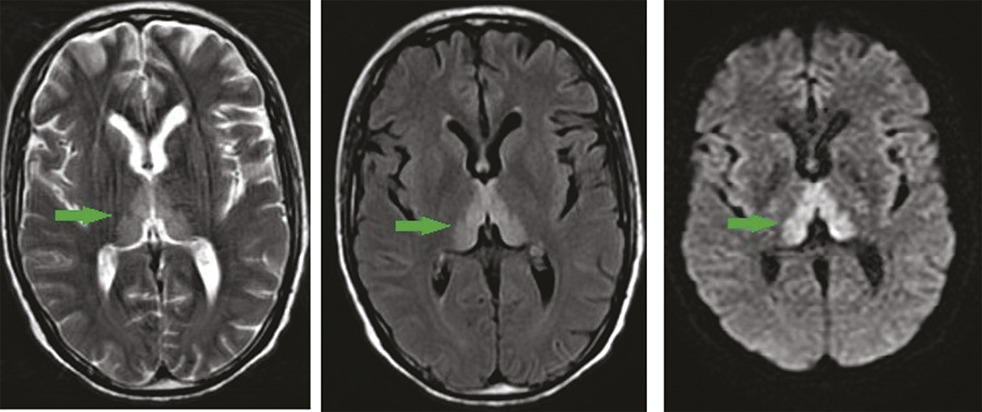

Ce patient de 49 ans, ayant bénéficié d’une duodénopancréatectomie céphalique pour un ampullome vatérien, était admis pour des vomissements incoercibles apparus en postopératoire immédiat, rebelles au traitement, et mis sous nutrition parentérale. Une semaine plus tard apparaissait un syndrome confusionnel avec apathie et hypersomnie. L’imagerie par résonance magnétique (IRM) montrait des hypersignaux T2, Flair et diffusion, bilatéraux et symétriques du thalamus postéromédian, périventriculaires du troisième ventricule et périaqueducaux en hypersignal (fig. 1, 2 et 3 ). Devant cet aspect en imagerie, associé aux vomissements prolongés, à l’alimentation parentérale et aux troubles neuropsychiques, une encéphalopathie de Gayet-Wernicke était évoquée, et le patient mis sous thiamine, avec une bonne évolution.

L’encéphalopathie de Gayet-Wernicke est une urgence médicale due à une carence aiguë et massive en vitamine B1.1 En dehors de l’alcoolisme, ses facteurs de risque sont : chirurgie gastro-intestinale, vomissements chroniques, nutrition parentérale prolongée, jeûne prolongé, malnutrition, anorexie mentale, chimiothérapie, sida.2 Elle se manifeste par une triade associant à divers degrés des troubles neuropsychiques (confusion, apathie, bradypsychie, hypersomnie), des troubles oculomoteurs et des troubles de l’équilibre. L’IRM cérébrale objective classiquement des hypersignaux symétriques dans les séquences pondérées T2, Flair et parfois une diffusion, de part et d’autre du troisième ventricule, des noyaux thalamiques postéromédiaux, des corps mamillaires, et de la région périaqueducale.1 Son traitement est fondé sur l’administration de thiamine.